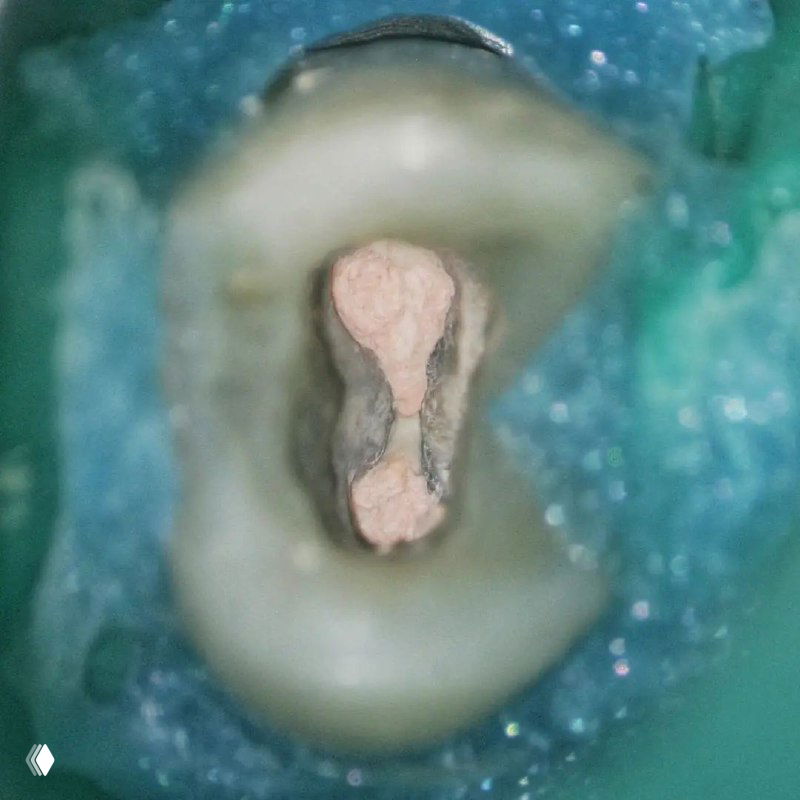

- классическую овальную полость доступа нужно немного расширить в области щёчных каналов в мезио-дистальном направлении

- проводить аккуратное расширение щёчных каналов, так как в области данных корней очень мало дентина (в моём случае расширение 25.04)

- аккуратно латералить без лишнего давления, а для вертикалки использовать самые тонкие плаггеры. А в идеале сделать гибрид.